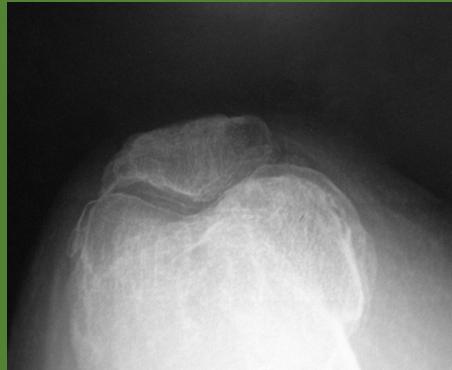

| Look | Compare both limbs, Skin, Muscle bulk, bony landmarks, hair distribution | Assess symmetry, signs of trauma, inflammation, muscle atrophy, structural changes | Visual examples - Skin, Muscle, Bone, Joint: ![]() ![]() ![]() ![]() ![]() ![]() | Swelling, scars, discoloration, hair changes, muscle wasting, bony protrusions, angulation, redness |

| Anatomic Examination: Bone (Patella, Tibial Tuberosity, head of Fibula) | Assess bony landmarks for tenderness or deformity | Bone Landmarks: ![]() | Tenderness, mass, crepitus, abnormal landmarks | |